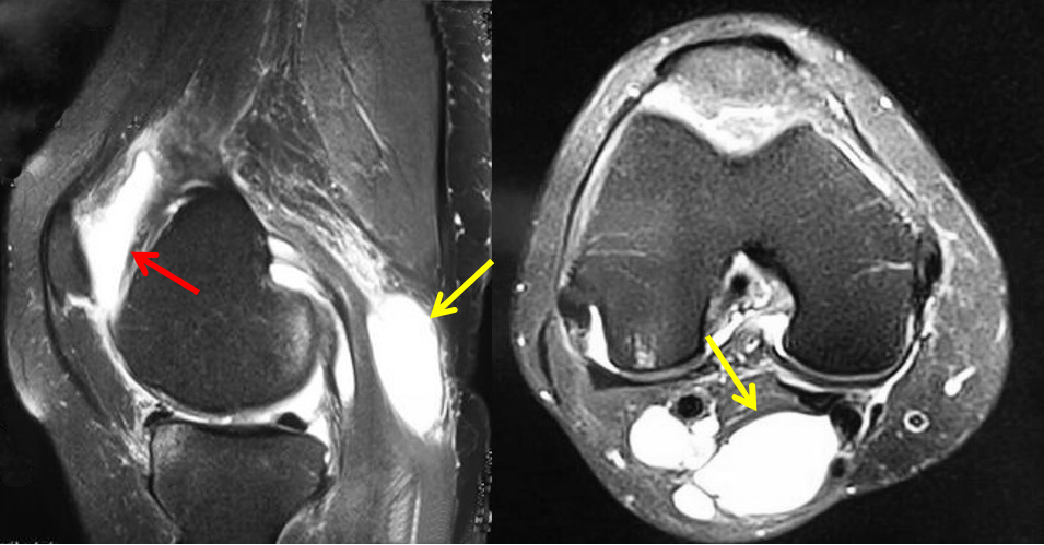

最近,張阿姨感覺到小腿窩酸脹不適,不能下蹲,還有點痛。她的膝關(guān)節(jié)本來就不好,以前還患過骨關(guān)節(jié)炎,莫非這次增生加重了?帶著這些疑惑,張阿姨到醫(yī)院要求醫(yī)生給她做個膝關(guān)節(jié)磁共振檢查。結(jié)果,張阿姨不僅有骨性關(guān)節(jié)炎,而且發(fā)現(xiàn)了一個60×80mm的腘窩囊腫。

可以使用超聲檢查,但核磁共振檢查(MRI)是鑒定膝關(guān)節(jié)周圍腫塊的金標準檢查,對腘窩囊腫的診斷較為明確。